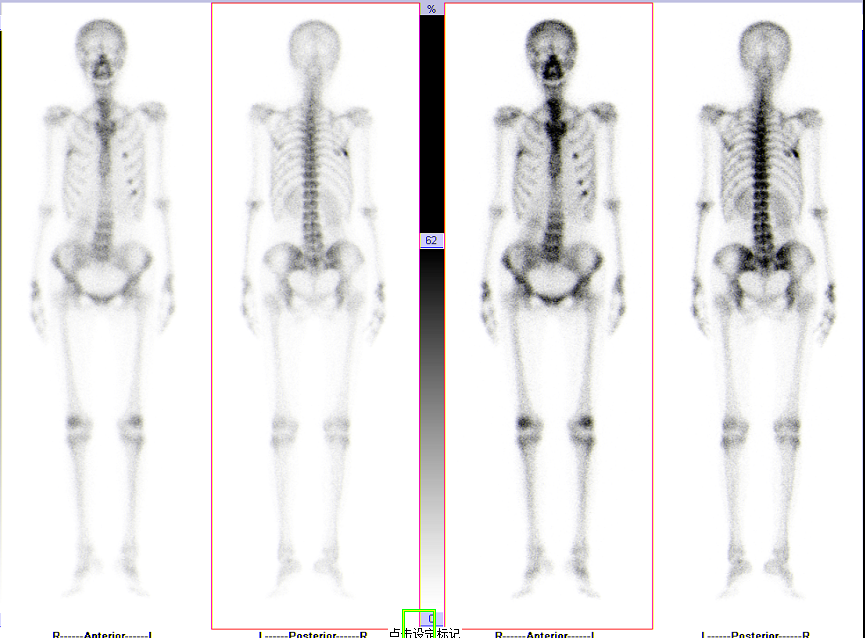

4.全身骨显像的一些表现

正常骨显像

全身多发骨转移

超级骨显像

肺性肥大性骨关节病